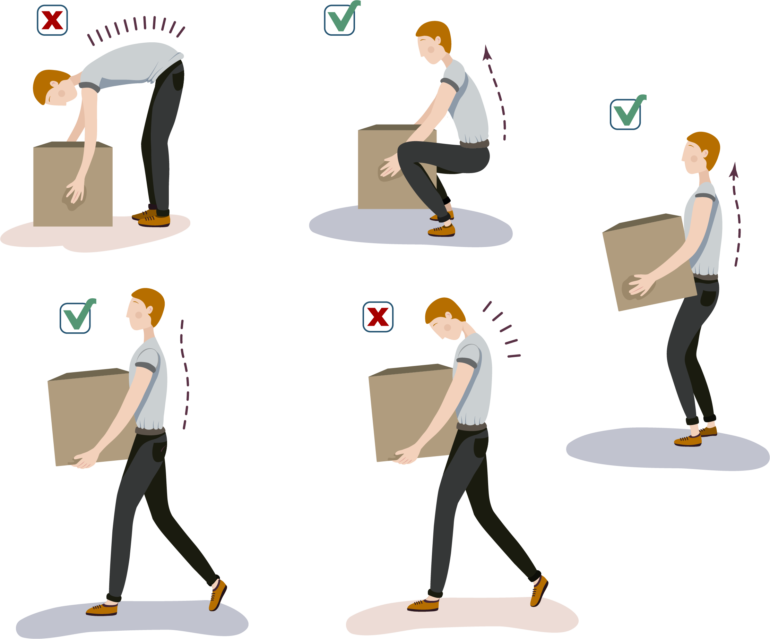

腰椎椎間板ヘルニアの主な原因は、椎間板にかかる強い圧力です。主には前屈みの姿勢で、急に重いものを持ったり、中腰や下を向く作業が多いと椎間板ヘルニアになりやすいと言われています。

弾力性のある椎間板を持つ若年層は、中腰で重いものを持ったときなど突発的に椎間板が飛び出してしまうことがあり、その場合激痛が走ります。

ヘルニアをきれいに取り除いても再発リスクがあります(5~10%程度)術後再発防止のため、当院では医師や理学療法士が日常生活の注意点などしっかりとアドバイスいたします。